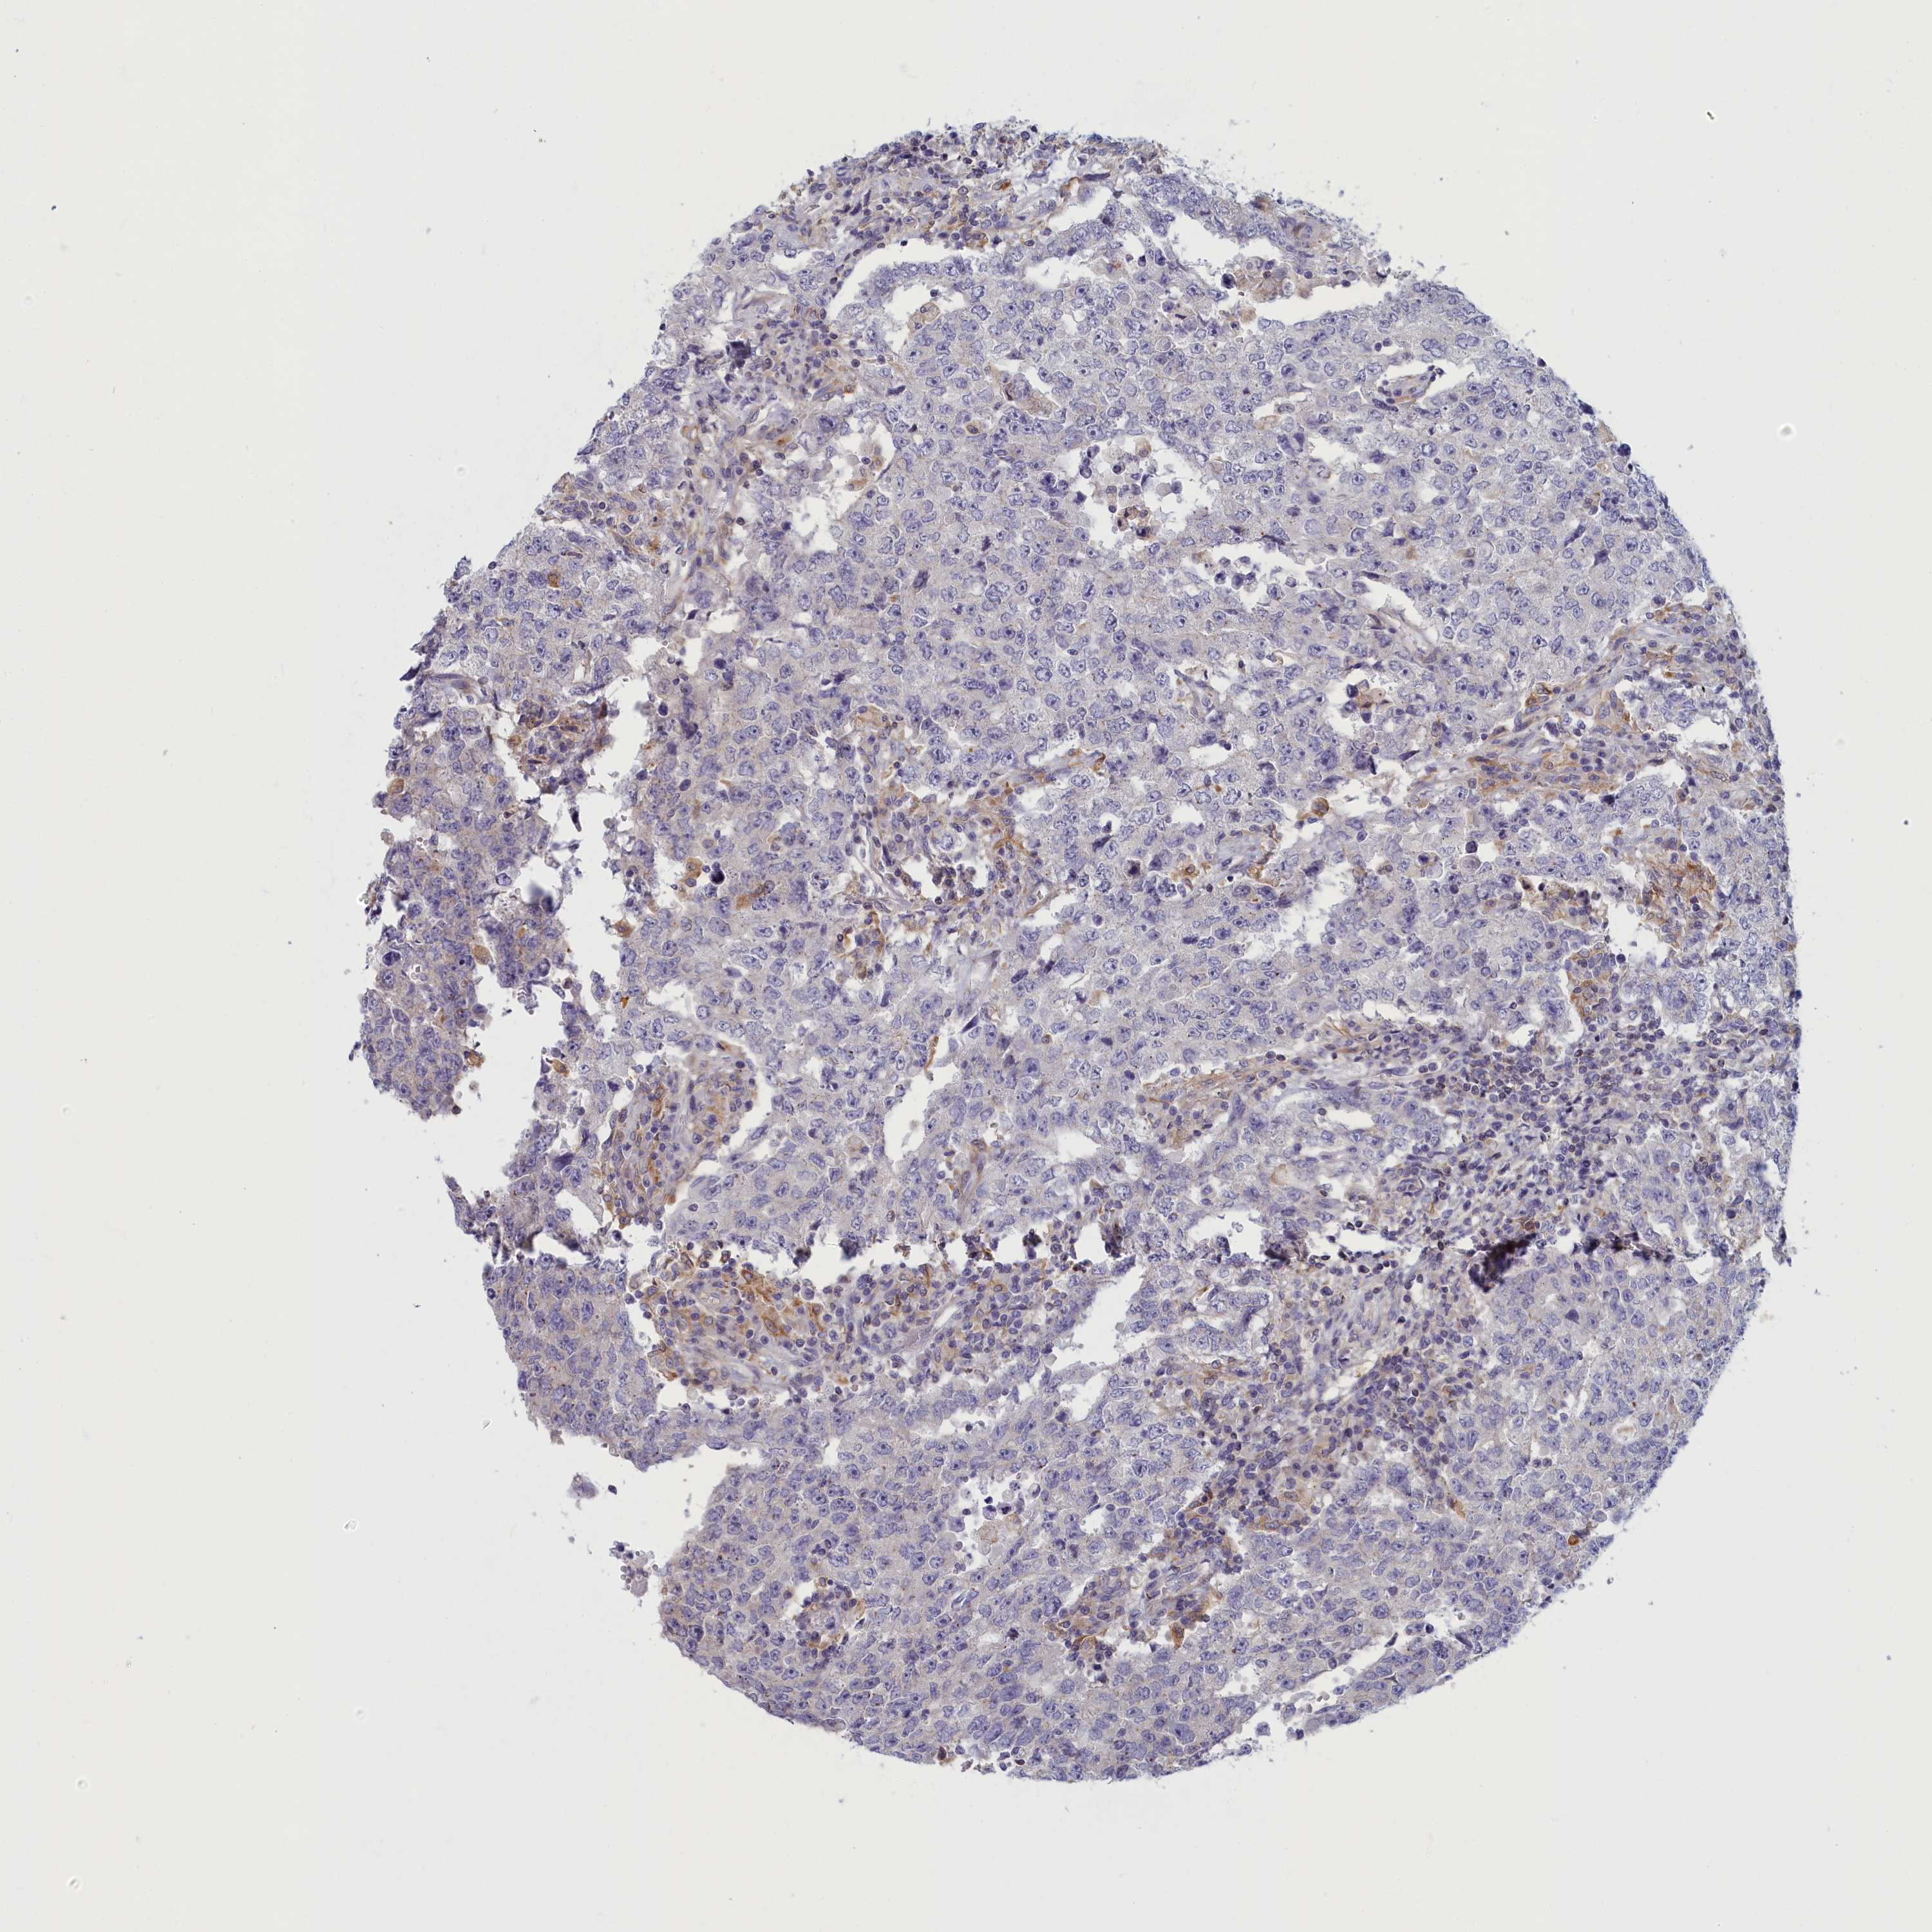

TESTIS CANCER - Protein expressioni

A mouse-over function shows sample information and annotation data. Click on an image to view it in a full screen mode. Samples can be filtered based on level of antibody staining by selecting one or several of the following categories: high, medium, low and not detected. The assay and annotation is described here.

Note that samples used for immunohistochemistry by the Human Protein Atlas do not correspond to samples in the TCGA dataset.

Antibody stainingi

Antibody staining in the annotated cell types in the current human tissue is reported as not detected, low, medium, or high, based on conventional immunohistochemistry profiling in selected tissues. This score is based on the combination of the staining intensity and fraction of stained cells.

Each image is clickable and will lead to virtual microscopy that enables deeper exploration of all samples and also displays staining intensity scores, fraction scores and subcellular localization as well as patient and tissue information for each sample.

Antibody HPA043075

Carcinoma, Embryonal, NOS

Seminoma, NOS